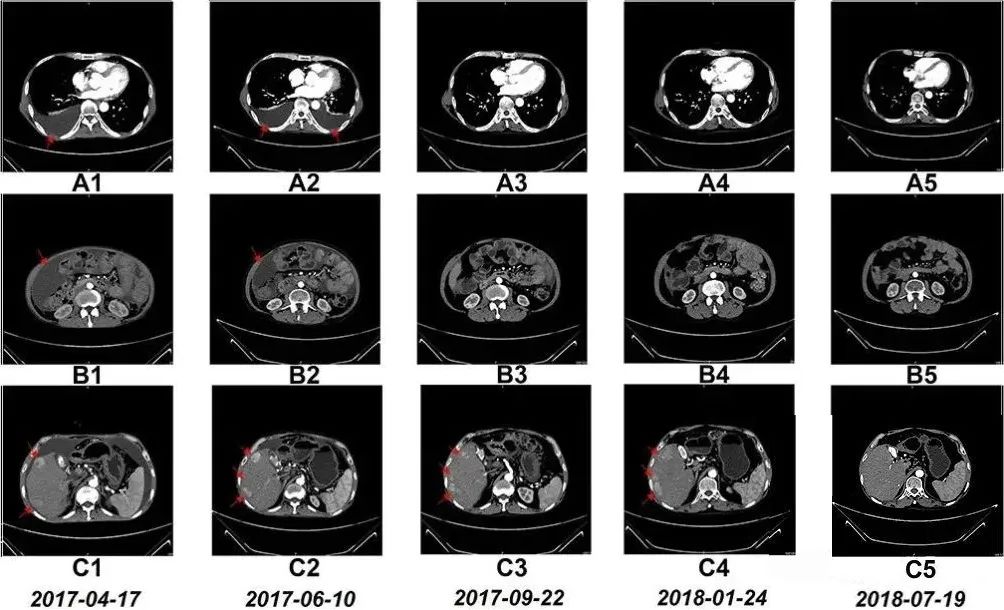

NK细胞治疗前和治疗期间的CT扫描结果

令患者本人和医疗团队都格外惊喜的是,7个月后,患者的胸水和腹水明显减少,治疗17个月后,CT扫描显示他肝右叶的多个肿瘤显著缩小。淋巴细胞亚群出现的变化表明免疫功能得到改善。此外,患者的肝功能水平和白细胞、血小板、中性粒细胞和淋巴细胞计数也保持在参考范围内。

上文提到的晚期肝癌患者程先生,正是通过15个月的NK细胞输注,使体内NK细胞比例提升近7倍,同时CD8+T细胞等关键免疫指标显著改善。影像学检查显示其胸腹水消退,肝部肿瘤缩小,生存期远超预期。